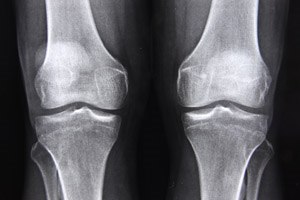

יום אבחון בכנסת: דלקות מפרקים

מחלות ראומטיות הן כבר מזמן לא נחלתם של קשישים בלבד....

אוסטיאוארתריטיס: נסו אבוקדו וסויה

נטילת תוספי מזון הכוללים תמציות של אבוקדו ופולי סויה...

אוסטיאוארתריטיס: כאב עד העצם וטיפול...

דלקת מפרקים ניוונית פוגעת בסחוסים המרפדים את עצמות ה...

דלקות מפרקים: כואב לא לדעת

70,000 ישראלים חולים בדלקת שדרה מקשחת הפוגעת בתפקוד...

דלקת מפרקים: איזו תרופה יעילה?

בישראל יש כ-70 אלף חולים בדלקת מפרקים שגרונית. לרשות...